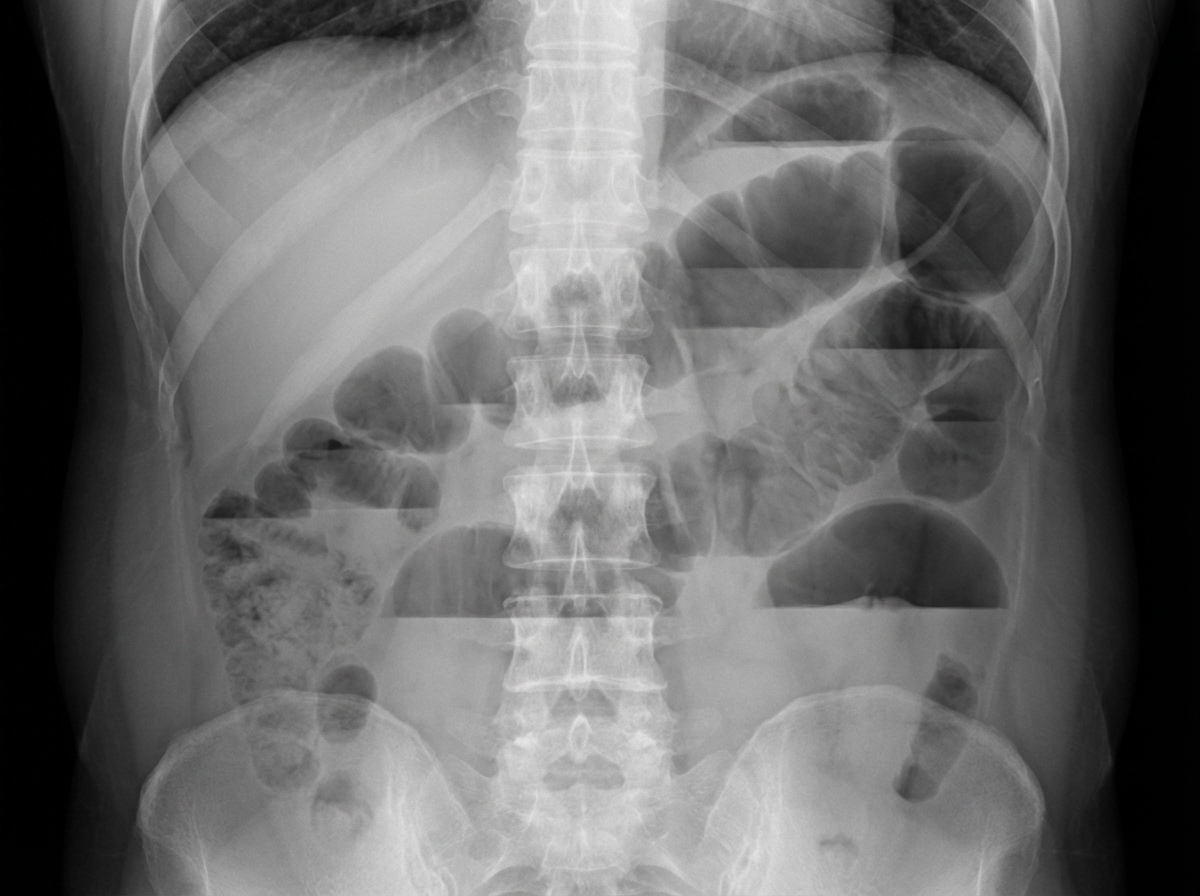

Which of the following is the most probable diagnosis based on the provided X-ray of the abdomen?

Explanation: ***Multiple air-fluid levels, suggestive of adhesions and bands*** - **Multiple air-fluid levels** in a **stepladder pattern** on erect abdominal X-ray is the classic radiological finding of **small bowel obstruction**. - **Adhesions and bands** are the most common cause of small bowel obstruction, especially in patients with previous abdominal surgery. *Gas under the diaphragm, suggestive of peritonitis* - **Pneumoperitoneum** (gas under diaphragm) indicates **bowel perforation**, not bowel obstruction. - This finding would appear as **crescent-shaped radiolucency** beneath the diaphragm on erect chest X-ray or abdominal X-ray. *Bird beak appearance, suggestive of volvulus* - **Bird beak sign** is seen on **barium enema** or **CT scan**, showing the twisted bowel segment in **sigmoid volvulus**. - This finding is not typically visible on plain **abdominal X-ray** and represents a different pathophysiology than adhesive obstruction. *Normal X-ray, PA view* - A normal X-ray would not show **air-fluid levels** or other signs of bowel obstruction. - The presence of multiple air-fluid levels clearly indicates **pathological findings** inconsistent with a normal study.